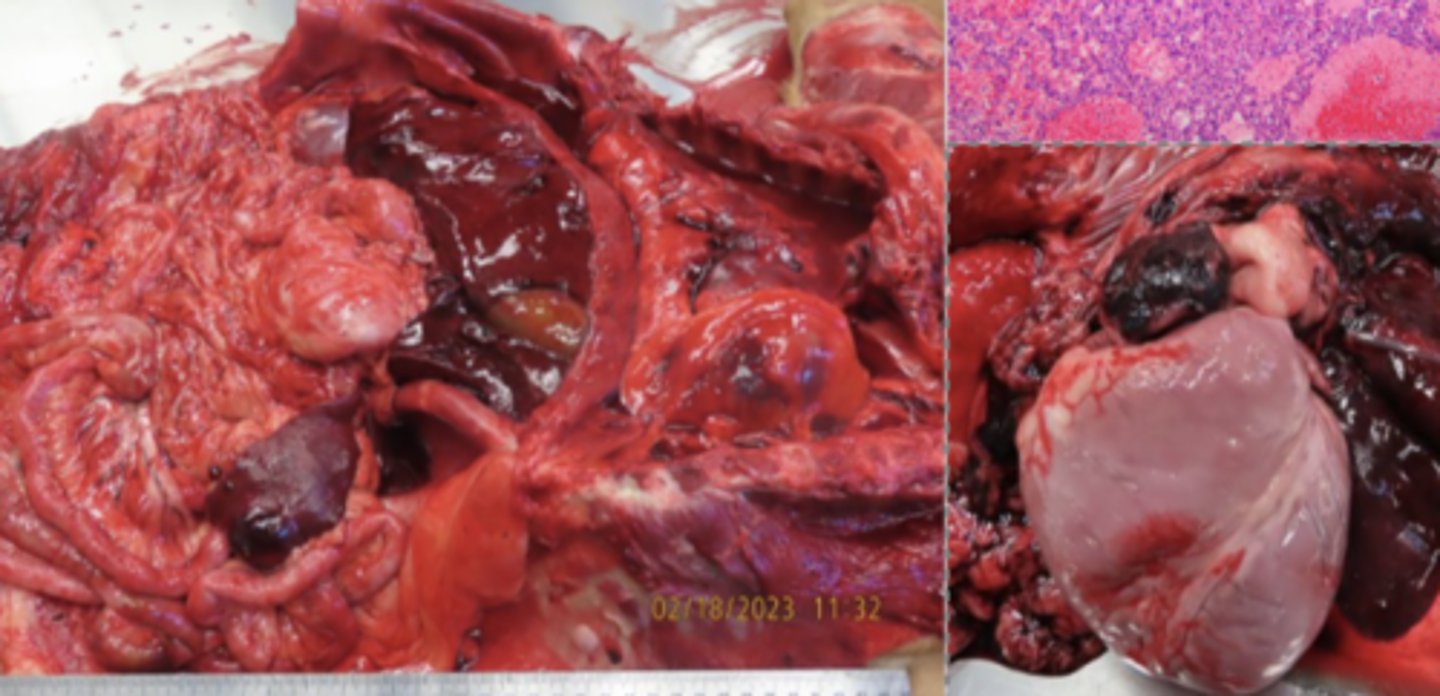

spleen, diffuse enlargement, rounded edges, mottled red color

splenomegaly - splenic lymphoma

Describe this lesion + diagnosis